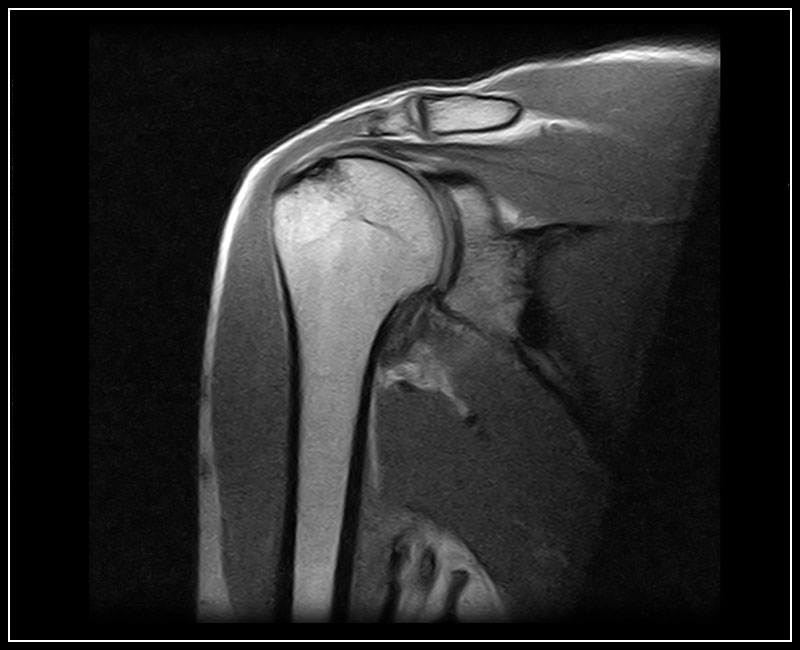

Klinické snímky

Technologie, příslušenství a snímky

G-scan Brio je speciálně navržen pro všechny aplikace pohybového aparátu. Otevřený a naklápěcí design je nový a inovativní způsob provádění MRI, při kterém se poloha pacienta stává nedílnou součástí výsledku vyšetření. G-scan Brio poskytuje pacientovi vysoký komfort s funkcí nejnovějšího zobrazovacího výkonu a sekvencí společnosti Esaote.